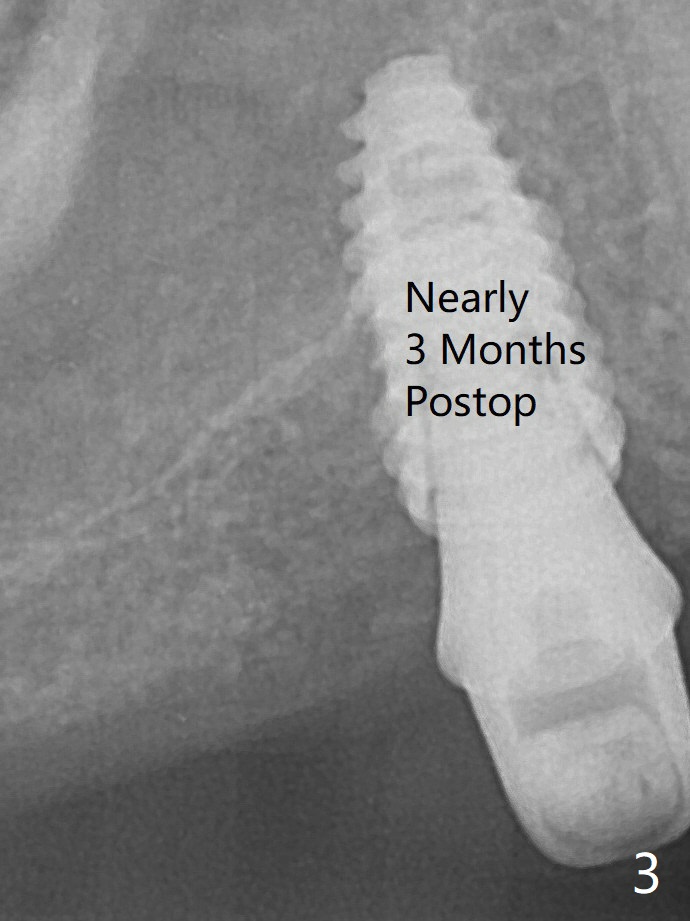

Osteotomy at #3 is performed last (Fig.1,2); as planned, a 4 mm cortical tap is used with guide for sinus lift. Unfortunately the sinus membrane is perforated. Implant placement is aborted. Instead Osteogen plug is inserted into the osteotomy, which is fixed in place by acrylic extending from the provisional at #4. Osteotomy for #3 implant will be attempted with control of the depth in 4 months. The patient has allergy to Amoxcillin (rash). When switching to Clindamycin, she develops diarrhea and loses 10 pounds. There is no abnormality at the site of #3 or 4 nearly 3 months postop (Fig.3). The next surgery will be most likely conducted without antibiotic.